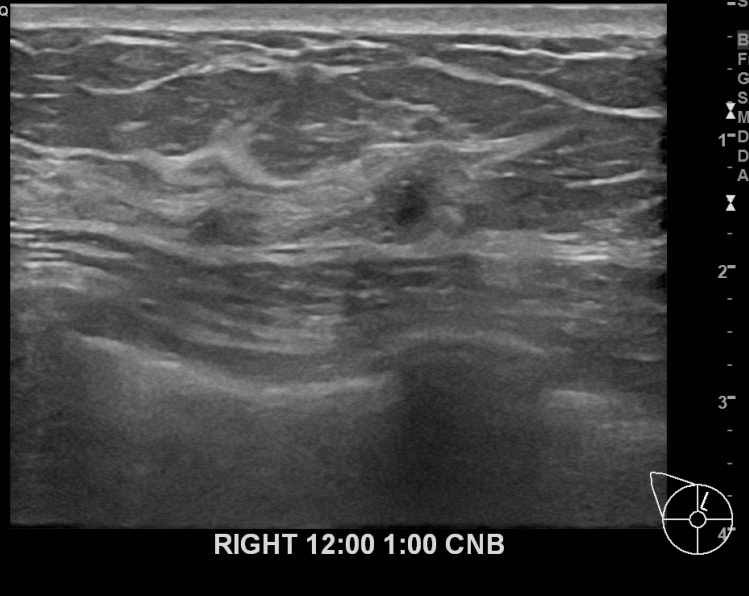

상기환자 외부검사이상소견으로 내원하신 60대 여성분으로 우측 조직검사 시행후

유방암 진단되셨습니다 .